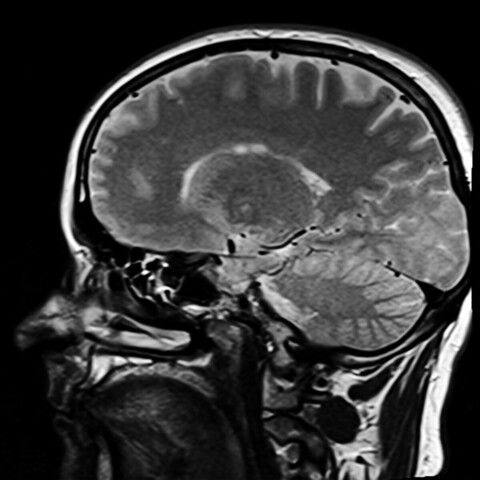

Разработка позволяет вычислить разницу между хронологическим и когнитивным возрастом. У пациентов с деменцией система зафиксировала ускоренное старение мозга в среднем на 15,4 года, а у людей с умеренными когнитивными нарушениями — на 7,6 года. Используемый SHAP-алгоритм показывает, какие именно функции (скорость распознавания цвета, устойчивость внимания или моторная реакция) дали основной вклад в отклонение.

Как отметил директор НИИ биологии старения ННГУ Михаил Иванченко, снижение скорости реакции, ухудшение памяти и цветового зрения может быть связано не только с естественным старением, но и с развитием деменции, последствиями диабета, депрессии или нарушений сна. Бесплатный инструмент доступен любому пользователю, что позволяет проводить персонализированную профилактику нейродегенеративных заболеваний.